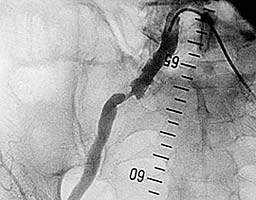

Пациент с жалобами на перемежающуюся хромоту,

боли возникают после ходьбы 100м.

На ангиограмме - субтотальный стеноз устья

правой наружной подвздошной артерии (рис.1).

Рис. 1 |